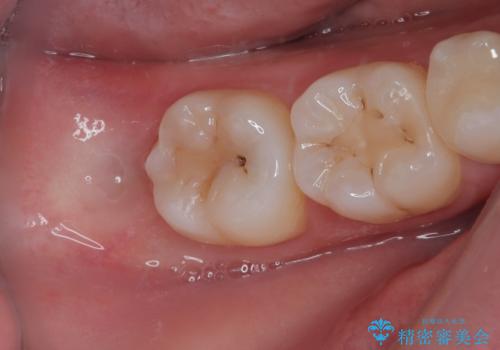

左下が虫歯になっている気がする オールセラミッククラウン

担当医 有澤哲郎